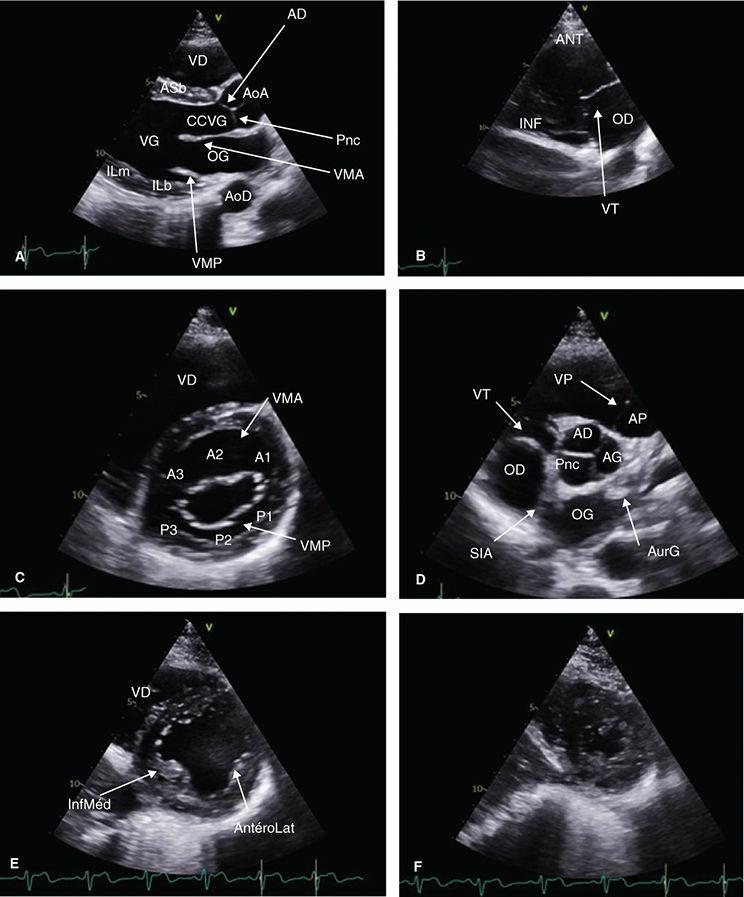

FIGURE11 Coupesparasternalesbidimensionnelles

Coupesgrandaxegauche(A),centréesurlescavtésdroites(B),petitaxecentréessuravavemtrale(C),avaveaortique(D),espiliersmitraux(E)etl'apex(F)AD:sigmoïdeantéro-droite;AG: sigmoïdeantéro-gauche;AoA:aorteascendante;AoD:aortedescendante;AP:artèrepumonaire;AS:antéroseptale;AurG:auricuegauche;b:basal;CCVG:chambredechasseventriculaire gauche;IL:inféroatéra;m:médian;OD:orellettedroite;OG:orellettegauche;Pnc:sigmoïdepostérieurenoncoronaire;SIA:septuminteratrial;VD:ventricuedroit;VG:ventriculegauche; VMA:valvemitraleantéreure(A1-A3);VMP:valvemitralepostérieure(P1-P3);VP:valvepumonaire;VT:vavetricuspde

PSGAgauche:visualisationduVD,duSIV(paroiantéroseptale),cavitéventriculairegaucheetparoiinférolatéralebasaleetmédiane,ainsiquedelaorte ascendanteaveclavalveaortique

Enbecquantlasondeverslebas:coupe2cavitésVD:visualisationdesparoisantérieureetinférieureVDetdelavalvetricuspide(figure11B)

Rotationdelasondeà90°danslesenshoraireàpartird'unePSGAoptimale,sinonrisquedecoupetangentiellenonperpendiculaireaugrandaxeduVG(figure 12Aet12B),visualisationdelavalvemitraleantérieureetpostérieureenmuseaudetanche(figure11C)

▪ Enbecquantverslehaut,valveaortiqueavecses3feuillets(figure11D),signedela«Mercedes»,avecnotammentl'antérogauche,cravatéeparl'infundibulum aveclavalvepulmonaireetletroncdelartèrepulmonaire

▪ Enbecquantverslebas,leVGauniveaudespiliers(antéro-latéraletinféromédian)(figure11E)

Enbecquantencoreverslebasouendescendantdunespaceintercostal,segmentsapicauxVG(figure11F)